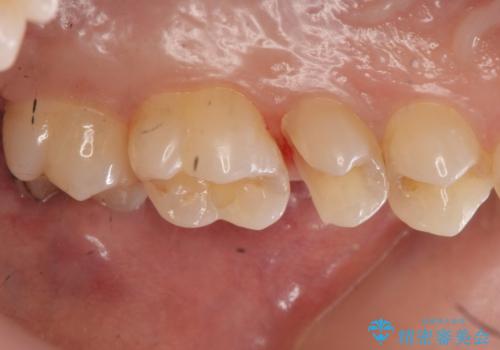

- 全体的にむし歯を治していきたいとのことで来院。

検査の結果、症状はないものの右上の奥歯に虫歯が見つかりました。

笑うと外からも見える位置であるため、白いセラミックでの治療となりました。

局所的に深い虫歯が確認されましたが、神経は温存することができました。

歯と歯の間から広がる虫歯は目視では確認しにくいため、定期的にチェックし悪化を予防することが大事です。